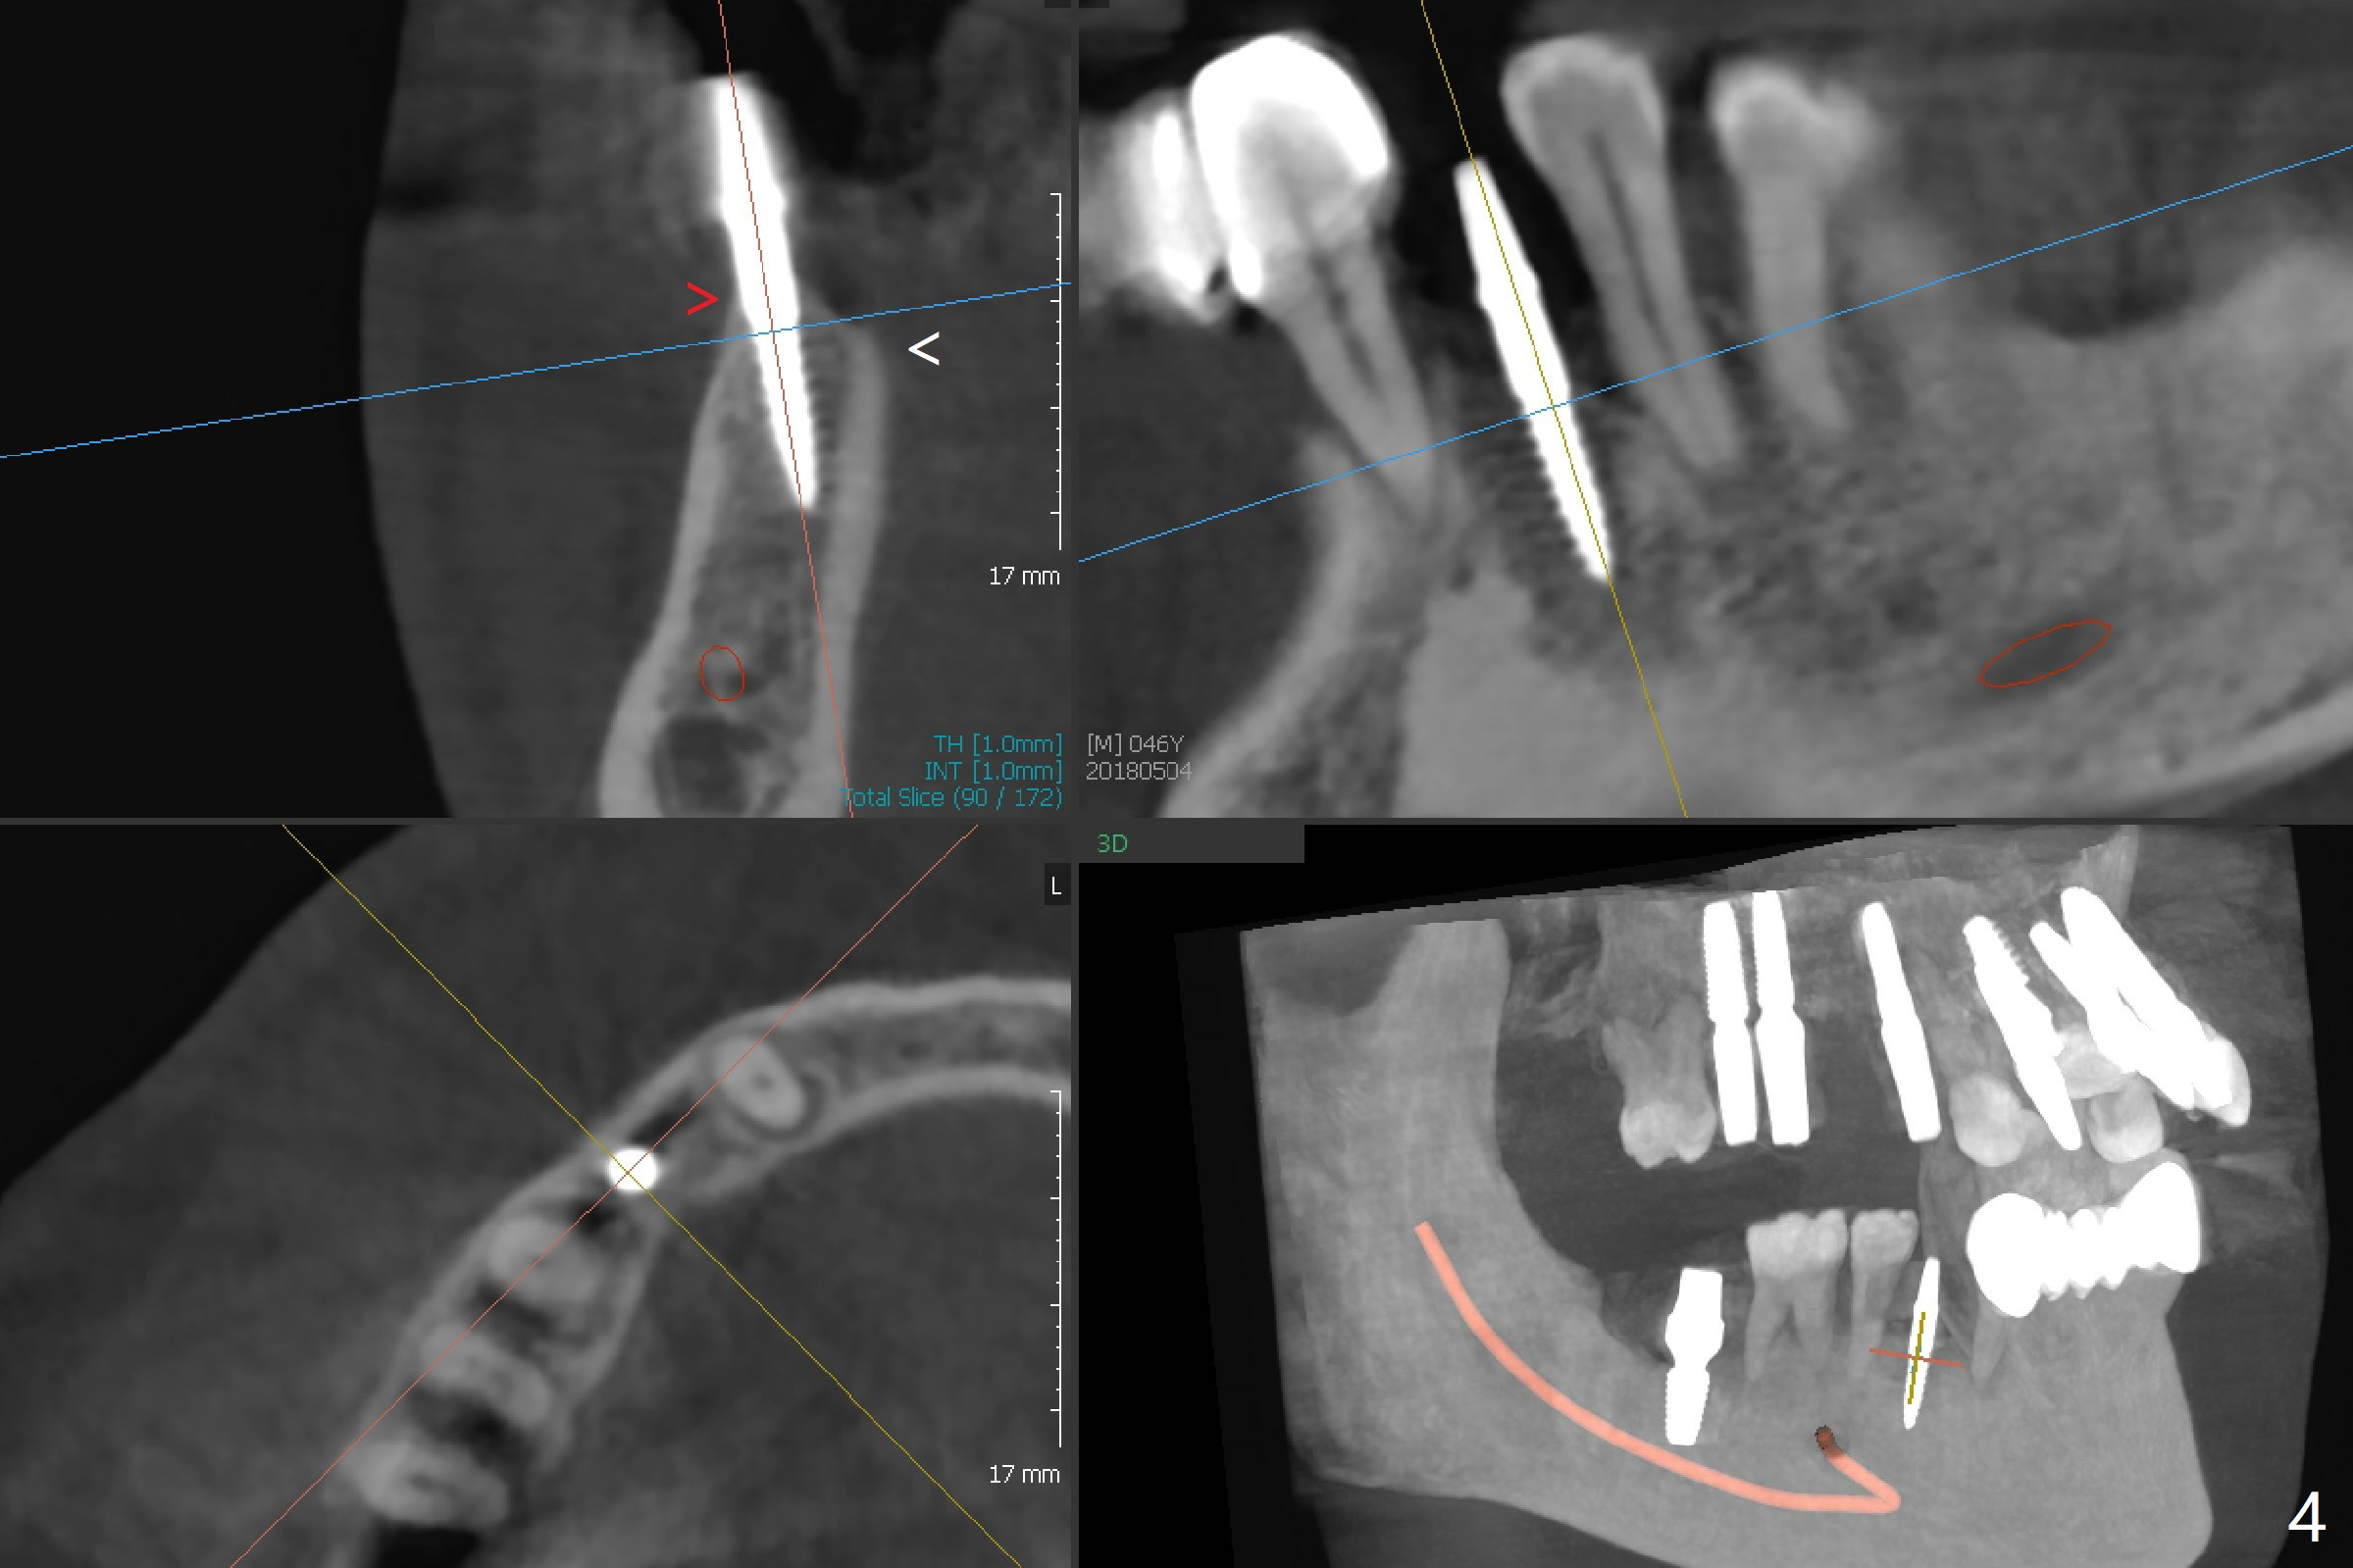

When flaps are raised at #28, the ridge appears to be narrow. Severe ridge resorption occurs 1-2 years post exfoliation. After ridge reduction, osteotomy is initiated mesially (Fig.1 (broken drill as a parallel pin)). A new osteotomy is going to be initiated as indicated by a blue line in Fig.1. It is done close to what is expected (Fig.2). When a 2.5x10(4) mm 1-piece implant is placed <20 Ncm, a major concern is where the Mental Loop is. To answer the question, intraop CBCT is taken (Fig.4). It appears that the ridge has not resorbed. If palpate more lingually (Fig.4 white <), the ridge would be found not so narrow. Preop and intraop panoramic X-ray film show sufficient bone height at the site (Fig.5,6). Low torque may be associated with low postop bone resorption, but it will take long to restore the implant.